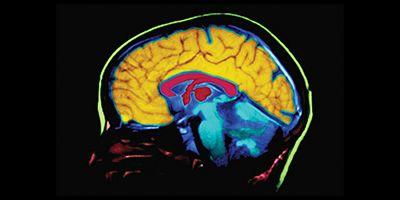

El fármaco, conocido como Aduhelm, fue aprobado por la FDA a pesar de la controversia y las críticas. Aduhelm promete atacar las placas de beta-amiloide en el cerebro, que se cree son una de las principales causas del Alzheimer. Sin embargo, la aprobación se dio a pesar de la falta de consenso en la comunidad científica sobre su efectividad real.

La polémica se intensificó cuando una investigación crítica que respaldaba la eficacia del fármaco fue retirada. Este estudio había sido fundamental para la aprobación del medicamento, proporcionando datos que sugerían que Aduhelm podría reducir las placas de beta-amiloide en el cerebro. Sin embargo, tras una revisión más detallada, surgieron preocupaciones sobre la validez de los resultados y la metodología utilizada.